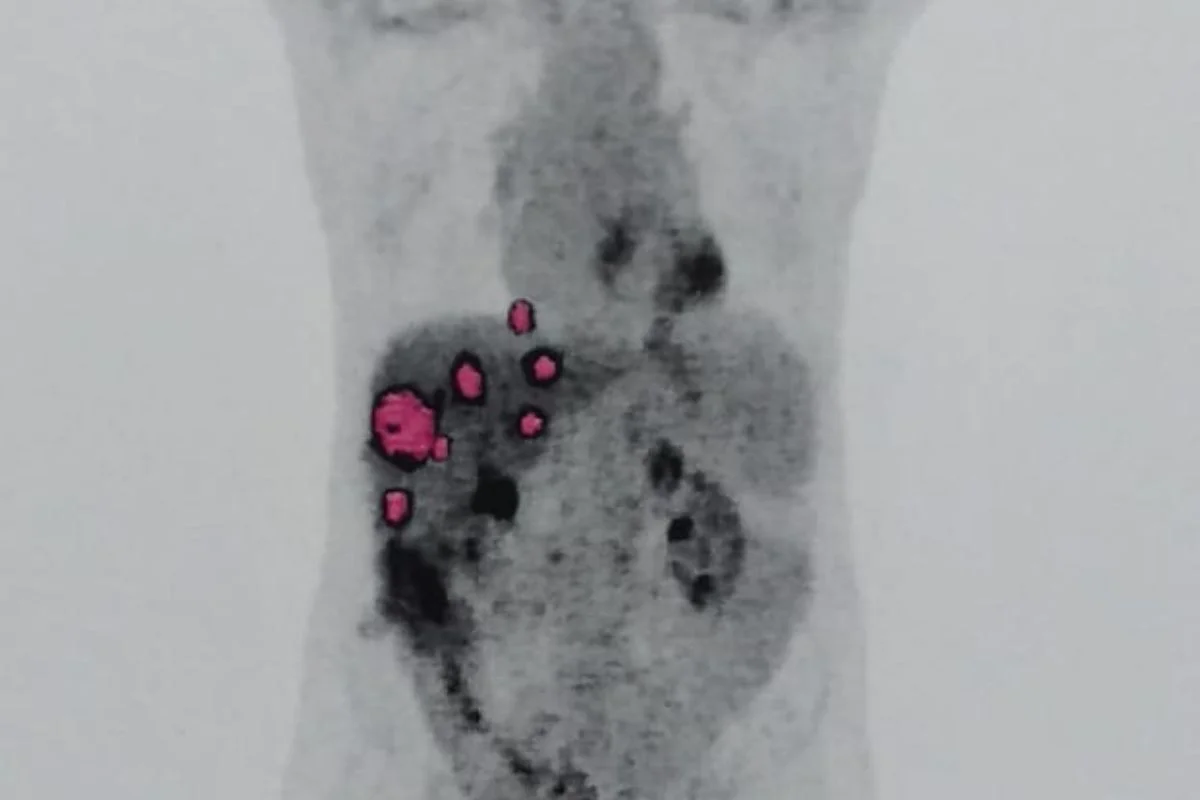

Geraldo enfrenta metástase de adenocarcinoma sem chance de cura, diz esposa

No início de agosto de 2024, veio mais um susto: foi detectada metástase no pulmão do paciente. A conclusão diagnóstica indicou um adenocarcinoma invasivo com as mesmas características das células cancerígenas do fígado transplantado.

“Isso sugere que a doadora já tinha um câncer que não foi detectado antes da doação, e pequenas células desse tumor estavam presentes no fígado transplantado”, explicou Caroline.